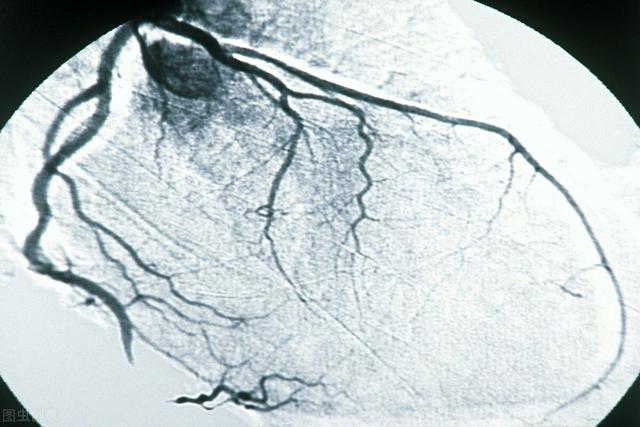

3. examen par tomodensitométrie coronaire :

La naissance de la tomodensitométrie à 64 rangs et le développement de la technologie de suivi dynamique nous ont permis d'examiner les vaisseaux cardiaques de manière non invasive afin d'identifier la présence et l'étendue de la sténose dans les vaisseaux coronaires. Cette technique a bénéficié à de nombreux patients souffrant d'oppression et de douleurs thoraciques et ayant peur des aiguilles et du bloc opératoire. Le principe de cet examen est le suivant : un agent de contraste est injecté par voie intraveineuse et un balayage en spirale des vaisseaux coronaires remplis de produit de contraste est effectué par tomodensitométrie. Chaque tranche de balayage de l'artère coronaire est ensuite combinée pour former une image de l'artère coronaire grâce à la technologie de combinaison d'images.

Ce test est non invasif et sûr, mais il présente un certain nombre de lacunes, ① le contrôle du rythme 64 rangs CT exige que la fréquence cardiaque soit contrôlée à 60 battements / min ou moins, plus rapide 128 rangs et CT à double source exige également que la fréquence cardiaque soit contrôlée autant que possible dans les 70 battements / min ou moins ; ② Coronary CT entre le cœur de l'examen ordinaire et l'angiographie des artères coronaires, mais aussi et l'angiographie des artères coronaires, comme les dommages de rayonnement et de contraste, si les symptômes sont très clairs. Si les symptômes sont très clairs, il est préférable d'effectuer le test d'imagerie en plus de l'examen, qui peut également être traité directement ; ③ souvenez-vous de cette phrase, si le scanner coronaire indique que vous n'avez pas de maladie coronarienne, la crédibilité de cette phrase peut atteindre 99 %, mais si le scanner coronaire indique que vous avez une maladie coronarienne, la crédibilité de cette phrase n'est que de 70 %.

3、Coronary CT : elle injecte un agent de contraste par une veine superficielle et utilise l'imagerie par tomodensitométrie, de sorte que la sécurité est supérieure à celle de l'artériographie directe, mais comme l'image est synthétisée et qu'il existe certaines exigences en matière de rythme cardiaque, la performance diagnostique est plus faible que celle de l'artériographie coronarienne ;

5. angiographie coronaire par tomodensitométrie (CT coronary angiography)La procédure consiste à injecter un agent de contraste iodé dans un vaisseau sanguin. Elle consiste à injecter un agent de contraste iodé dans un vaisseau sanguin et à utiliser la tomodensitométrie (CT) pour examiner les artères coronaires afin de vérifier la présence de malformations, de ponts dans le myocarde, de plaques et de sténoses dans les artères coronaires. L'avantage de cette méthode est qu'elle est "non invasive" et qu'il n'est pas nécessaire d'introduire un cathéter dans les artères coronaires. Cependant, comme il s'agit d'une radiographie, il est préférable d'examiner les calcifications, mais il y a des limites à l'examen des sténoses, qui n'est pas très précis (cela dépend de l'instrument et du niveau de compétence de l'examinateur), et en outre, un rythme cardiaque rapide ou irrégulier affectera également l'effet de l'imagerie. Par conséquent, cette méthode est la meilleure pour exclure une maladie coronarienne et moins précise pour diagnostiquer une sténose. En outre, au cours de l'examen, 80 à 100 ml d'agent de contraste iodé sont injectés par voie intraveineuse. Premièrement, il existe un risque d'allergie (le test cutané peut ne pas être détecté), deuxièmement, l'agent de contraste doit être excrété par les reins, ce qui est dommageable pour les reins, et un petit nombre de patients peut développer une "néphropathie de contraste" (néphropathie de contraste), avec une déficience ou une insuffisance rénale, de sorte qu'un traitement d'"hydratation" est nécessaire avant et après l'examen. Il est donc nécessaire de s'hydrater avant et après l'examen.

- 冠Le CTA de Pulse est un plombier débutantL'angiographie coronarienne est en fait une sorte d'examen tomodensitométrique. Lors de cet examen, un médicament est injecté dans la veine de la main, ce médicament est l'agent de contraste. Lorsque l'agent de contraste atteint l'artère coronaire, il montre l'ombre de cette artère coronaire et permet de déterminer s'il y a un blocage ou un rétrécissement de l'artère coronaire.Les troncs principaux des artères coronaires et certaines des plus grosses branches sont plus clairement visibles, tandis que les plus petites branches sont moins bien représentées.

ATC coronaire

L'angiographie coronarienne par tomodensitométrie est un moyen d'examiner les artères coronaires en combinaison avec l'angiographie, ce qui permet de diagnostiquer la maladie coronarienne et d'examiner et de juger l'emplacement des plaques coronaires, en particulier l'étendue des plaques calcifiées. L'angiographie coronarienne par tomodensitométrie permet également d'évaluer si le flux sanguin est régulier au niveau du site du stent chez les patients atteints de maladie coronarienne et auxquels on a implanté des stents. En outre, pour les patients souffrant de douleurs thoraciques, l'angiographie coronarienne par tomodensitométrie permet de détecter des problèmes tels que l'aortique, le pneumothorax et le pneumothorax. Pour les patients souffrant de douleurs thoraciques, l'angiographie coronaire peut être utilisée pour dépister les problèmes aortiques, pulmonaires et de pneumothorax, mais elle n'est pas recommandée pour les patients présentant une forte suspicion d'infarctus aigu.

Cependant, pour une partie de la population qui ne présente pas de risque élevé de maladie coronarienne, les médecins recommandent parfois un dépistage de la sténose des artères coronaires à l'aide de la technologie CTA coronaire.Bien que la précision de l'angiographie coronaire soit encore loin de celle de la coronarographie, elle permet d'exclure les patients dont la coronaropathie est négative.